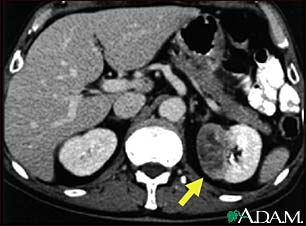

CT/MRI: